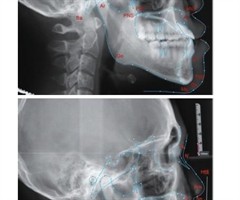

基于CBCT技术对维吾尔族和汉族成人不同骨面型下颌骨形态的不对称性研究

[摘要]目的:通过测量分析不同矢状、垂直骨面型的维吾尔族、汉族成人下颌骨形态,研究成人族别、骨面型对下颌骨不对称的影响。方法:根据纳入排除标准收集18~30岁维吾尔族、汉族(n=360)的下颌头颅定位侧位片和CBCT资料,使用Dolphin...

成人与青少年骨性Ⅲ类错牙合畸形患者掩饰性治疗后软硬组织和牙周情况对比分析

[摘要]目的:对成人与青少年骨性Ⅲ类错牙合畸形患者进行正畸掩饰性治疗,对比治疗前后软硬组织侧貌及牙周支持组织的变化,评价不同年龄组正畸治疗效果的差异。方法:选取2020年7月-2023年6月于无锡口腔医院就诊的40例符合研究标准的骨性Ⅲ类错...

安氏Ⅰ类双颌前突患者矫治前后软硬组织变化及疗效研究

[摘要]目的:分析正畸治疗安氏Ⅰ类双颌前突患者的临床效果及对软硬组织变化的影响。方法:选择2022年1月-2024年1月笔者医院收治的98例安氏Ⅰ类双颌前突患者,所有患者均接受正畸-正颌治疗,治疗前后接受X线头影测量,观察所有患者临床疗效和...